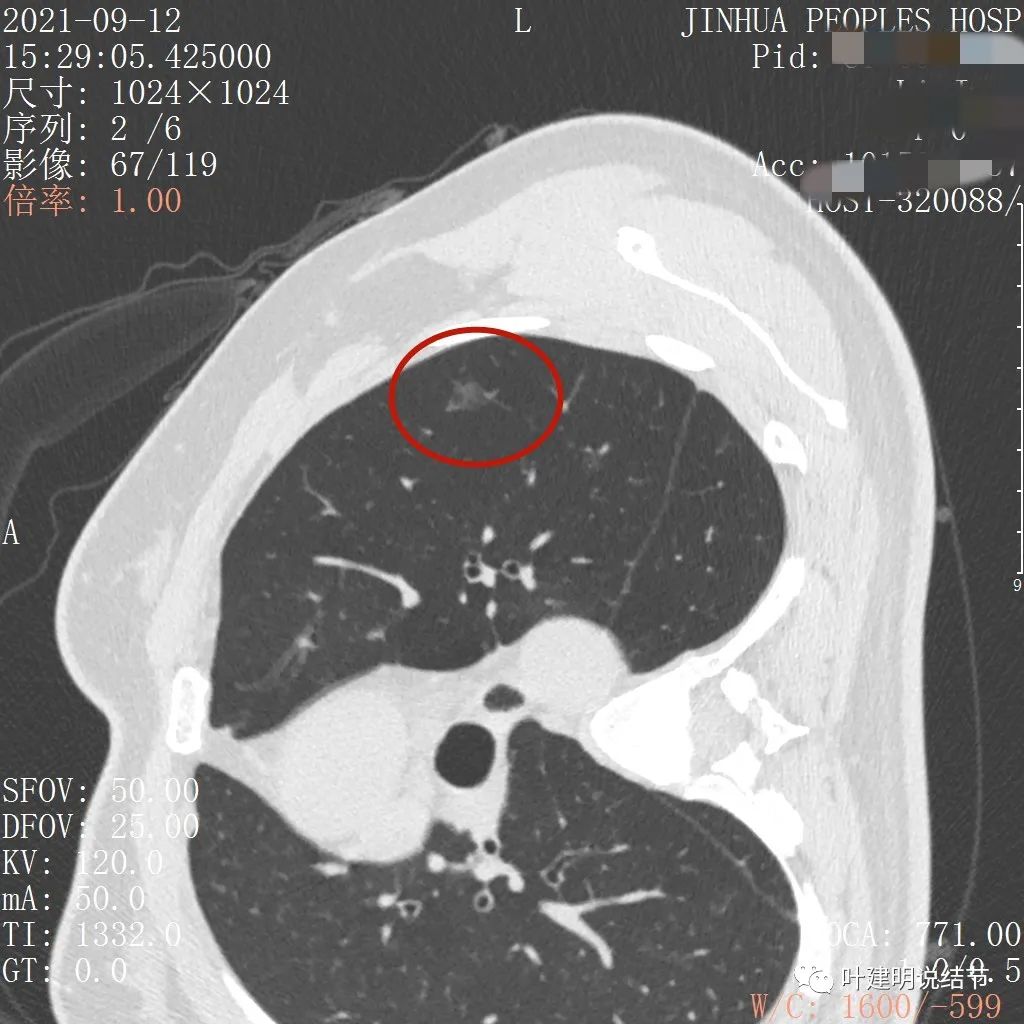

从以上靶扫描图像上看,给人的印象是肿瘤范畴的结节,是混合磨玻璃结节,但磨玻璃部分的密度偏低,有的边缘显模糊,中间有点状高密度,也有微小血管进入,应该至少微浸润性腺癌可能性大。持续存在已经2月余,位置又还靠边上的,可考虑手术切除。下面再来瞧瞧后处理重建的图像:

上图非常不舒服,病灶边缘有毛刺(蓝色箭头),中间有偏实性成分(粉色箭头所指),整体看密度不均杂乱

上图示明显的血管进入(桔色箭头),而且进入病灶后散大模糊,不是穿行;病灶内有高密度区域(粉色箭头)。但事后分析,绿色箭头所指的磨玻璃部分密度仍是过低,且边缘显模糊,与浸润性腺癌可能不是太符合。

以上三图均示典型的混合磨玻璃,实性成分杂乱,整体密度杂乱,并有血管征,是较为典型的浸润性腺癌影像表现。

看了后处理重建的图像,我们认为基本上应该就是浸润性腺癌了,从平扫到靶扫到靶扫描后处理,一步一步往更恶性的角度考虑。某A按我们的建议进行了单孔胸腔镜下手术,结果术中快速病理切片示:原位腺癌。我还觉得术后病理会不会升级,所以还在等石蜡切片,因为影像上,特别是后处理重建的图像太像浸润性腺癌了,结果仍是原位腺癌: